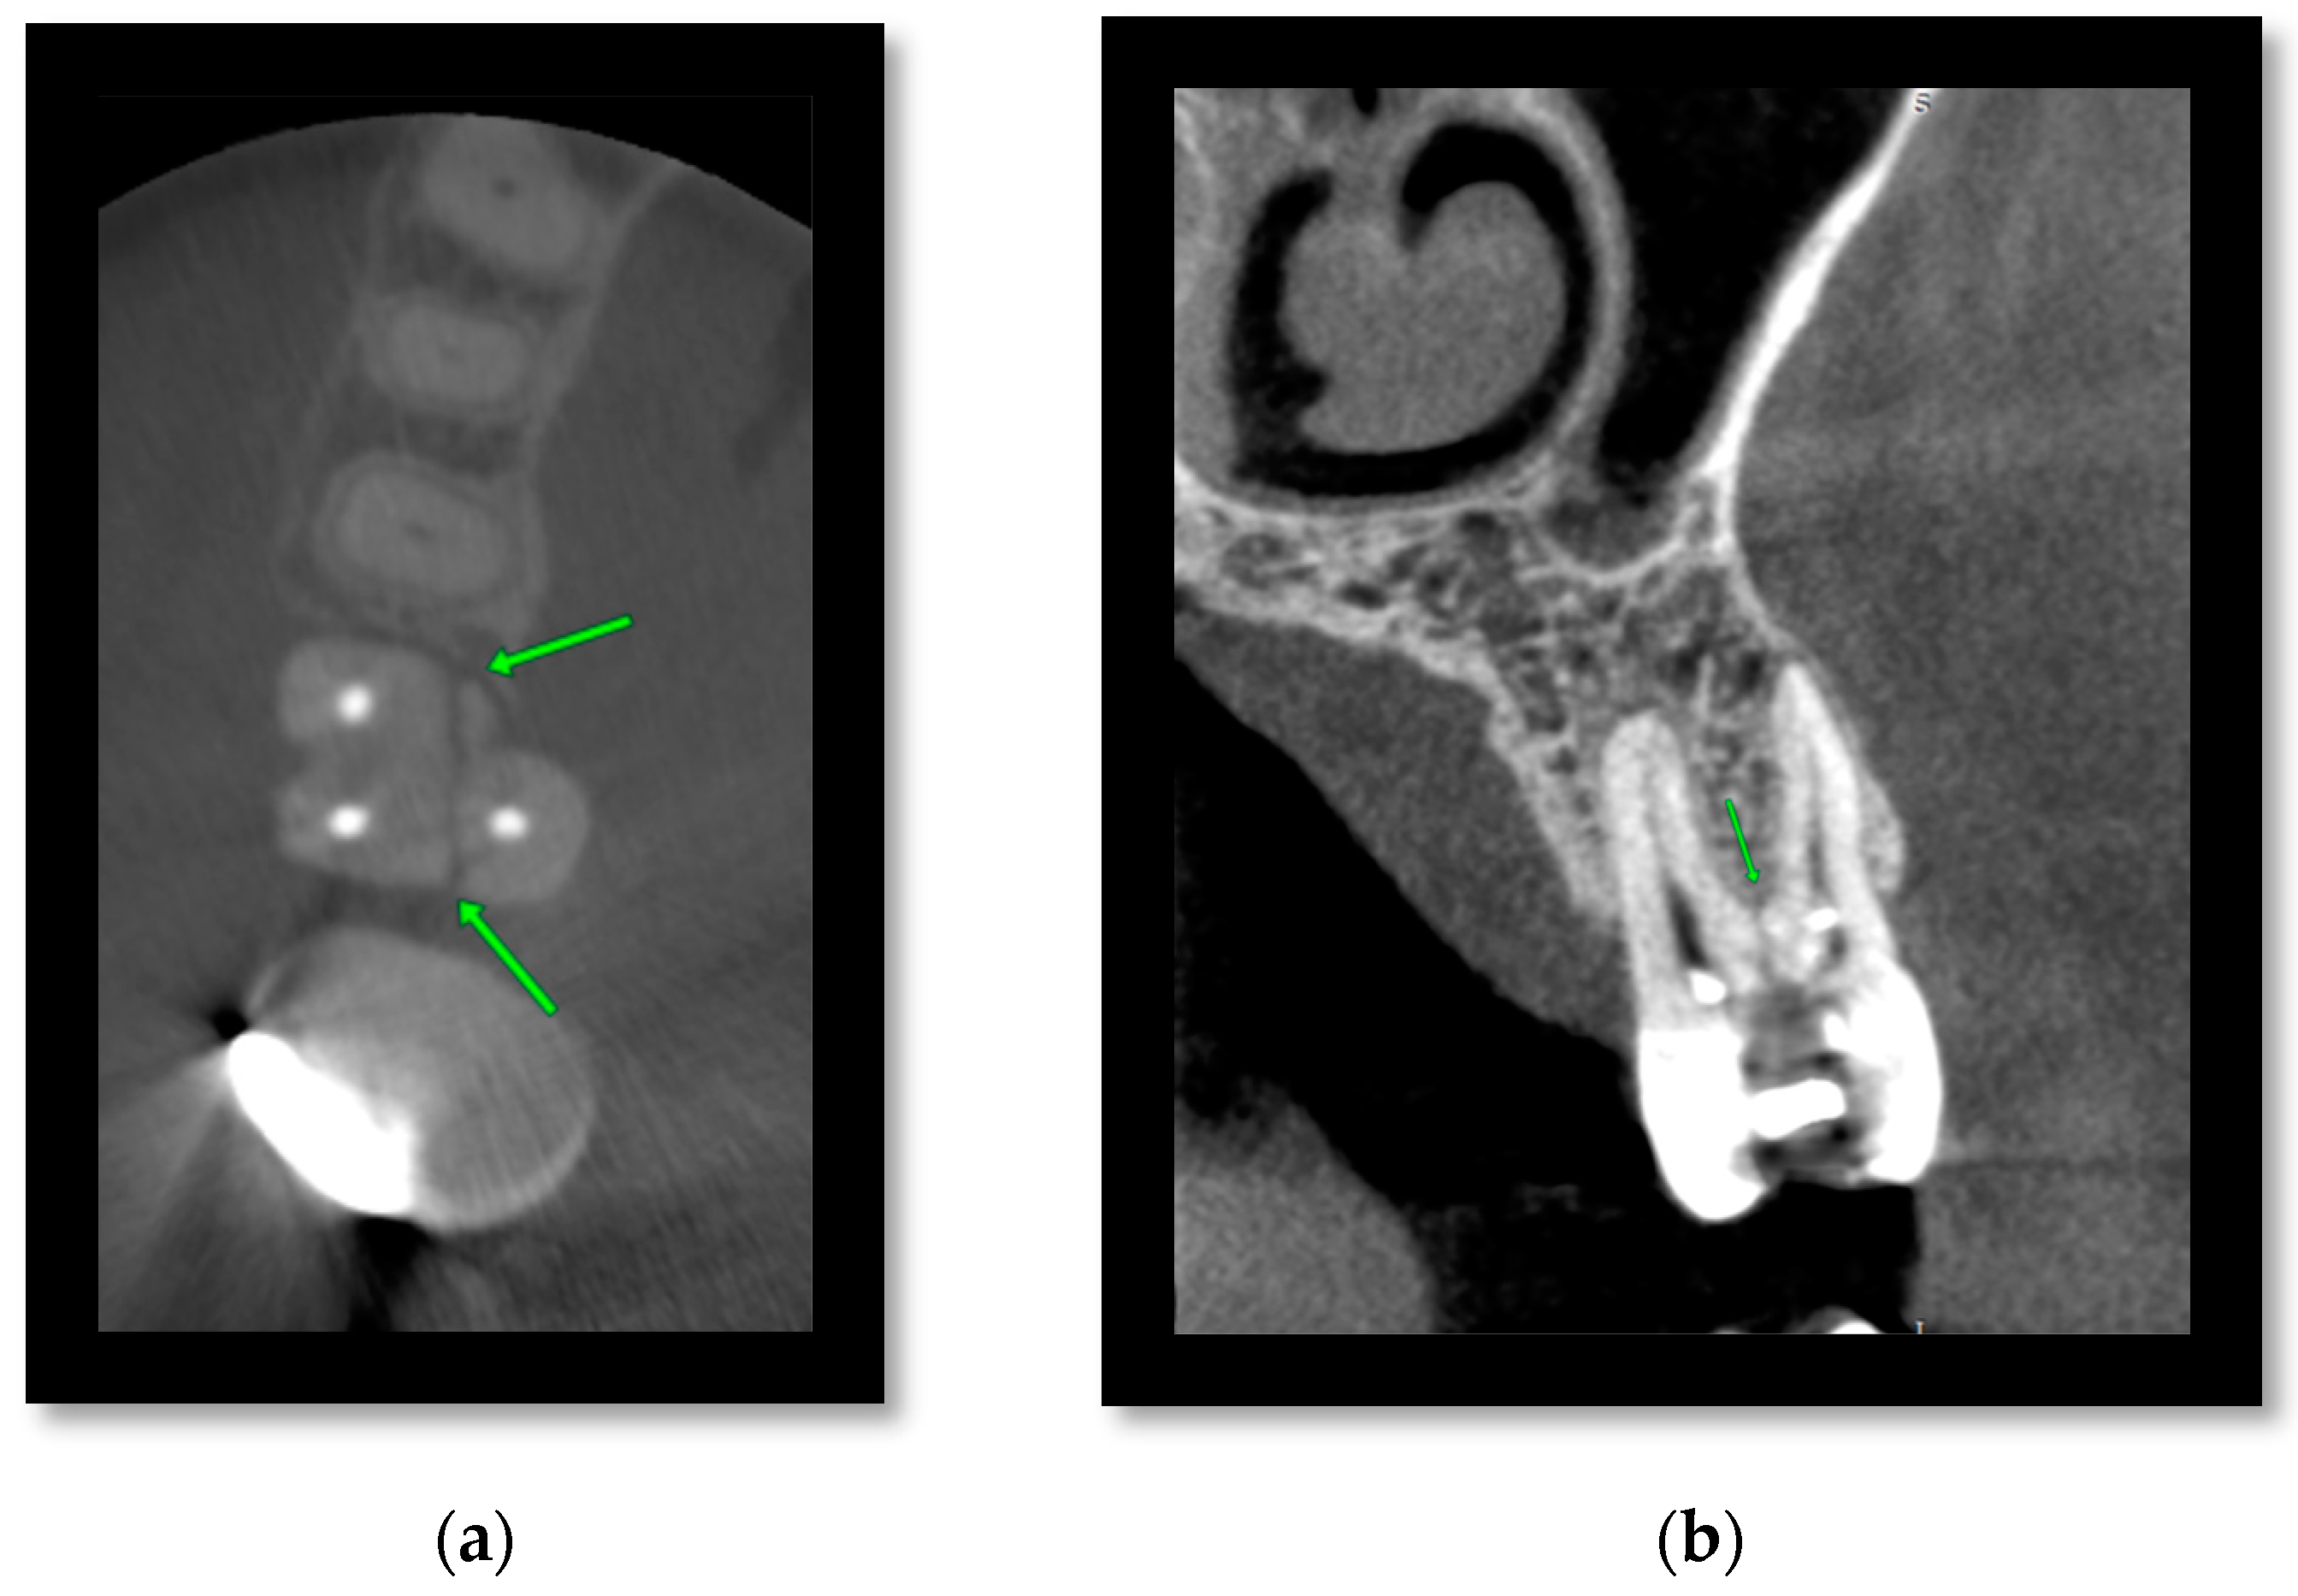

3.2. Cone Beam CT for Assessment of Mandibular Fractures

- Kaeppler, G.; Cornelius, C.-P.; Ehrenfeld, M.; Mast, G. Diagnostic efficacy of cone-beam computed tomography for mandibular fractures. Oral Surg. Oral Med. Oral Pathol. Oral Radiol. 2013, 116, 98–104. [Google Scholar] [CrossRef]

- Mahesh, K.; Viveka, S.; Patil, K. Probability prediction of nerve injury using CBCT images in mandibular fractures: An observational study. J. Indian Acad. Oral Med. Radiol. 2023, 35, 191–196. [Google Scholar] [CrossRef]